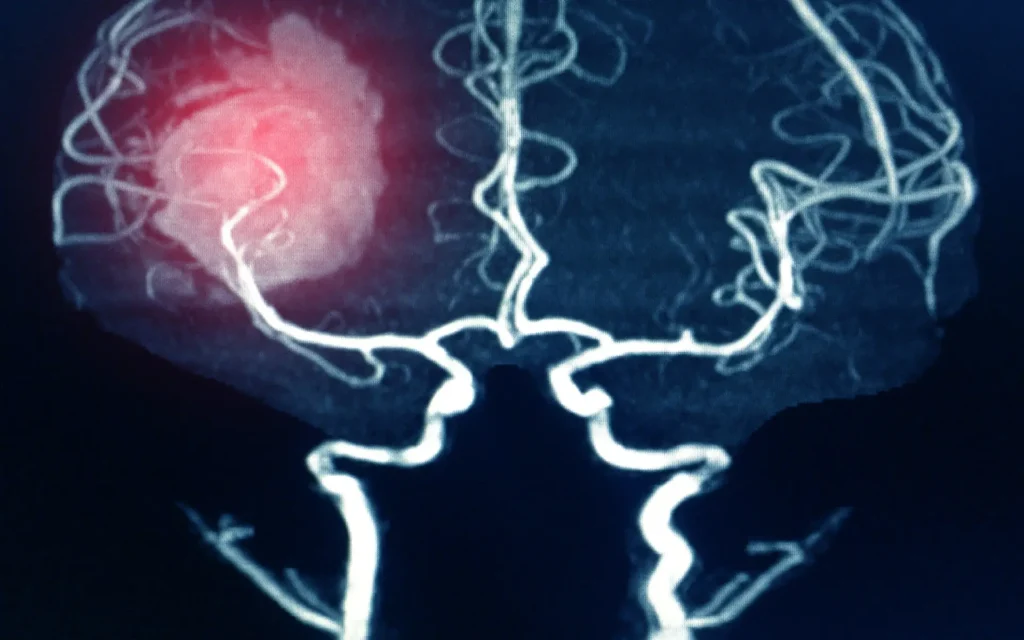

Aneurismas -

Cirugía Cerebral y de Base de Cráneo

Abordamos patologías cerebrales como tumores, aneurismas, epilepsia, cefaleas crónicas…

Neurocirugía Oncológica y

Vascular

Tratamiento quirúrgico y médico de tumores cerebrales, medulares y de la columna vertebral.